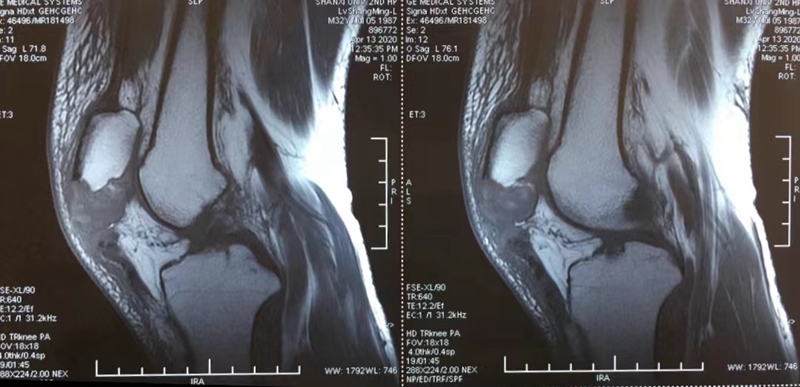

吕某,男,32岁,左髌骨下极撕脱骨折7天,2020年4月16行“双套固定法”手术。

术前资料